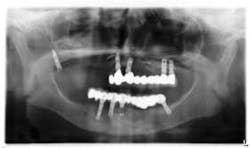

Under local anesthesia, a full thickness flap was elevated from the upper right to upper left posterior segments. Using a piezoelectric handpiece, a buccal window hinge osteotomy was elevated in the maxillary right posterior region. A mixture of DFDBA, anorganic bovine bone, and PRF was placed. A collagen membrane was used to cover the buccal window. Simultaneously, two puros J-block allografts were secured in the 5 to 7 and 10 to 12 region with stainless steel screws (1.6 x 8 mm screws). A mixture of DFDBA, anorganic bovine bone and PRF was placed over each area and covered with PRF sheet and a collagen membrane. Primary closure was obtained with CV-5 Goretex sutures. Healing was uneventful. After six months of healing, six straight implants were placed in sites 3, 4, 5, 6, 11, and 12. Healing abutments were placed at stage I. Healing was uneventful. After four months of healing, six custom abutments were fabricated by his dentist and cover screws were placed on implants 8 and 9 and converted into pontics.

Removing the implants would have created a large buccal defect, which would have created elongated pontics in the maxillary anterior region. The prosthesis was completed, and the patient is stable and highly appreciative of her ability to smile and chew.

Case 2: Sinus lift, bone graft, PRP, and after healing implant placement